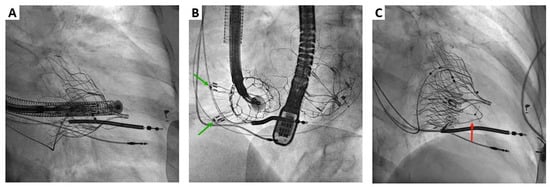

2. Cardiovalve Cases

4.2. Cardiovalve

- Barreiro-Perez, M.; Estevez-Loureiro, R.; Baz, J.A.; Piñón, M.A.; Maisano, F.; Puga, L.; Caneiro-Queija, B.; Iñiguez-Romo, A. Cardiovalve Transfemoral Tricuspid Valve Replacement Assisted With CT-Fluoroscopy Fusion Imaging. JACC Cardiovasc. Interv. 2022, 15, e197–e199. [Google Scholar] [CrossRef]